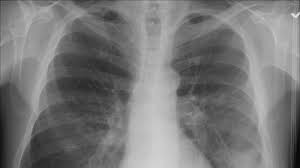

По факту госпитализации более 100 школьников с подозрением на пневмонию в Новгородской области начата доследственная проверка, говорится в сообщении регионального главка СКР 20 октября.

В правительстве Новгородской области уточнили, что с пневмонией в областную детскую клиническую больницу и областную инфекционную больницу госпитализирован в общей сложности 101 ребенок.

В целом, по данным Роспотребнадзора, с начала октября отмечен рост заболеваемости внебольничными пневмониями (острое инфекционное заболевание, возникшее вне стационара). Всего в Новгородской области за две недели октября зарегистрировано 185 случаев внебольничной пневмонии.

103 ребенка заболели в Великом Новгороде. А с января по сентябрь было зафиксировано 2,5 тыс. заражений по области, что на 8% ниже, чем за аналогичный период прошлого года. Резкая же вспышка заболеваемости в октябре вызвала интерес СКР.